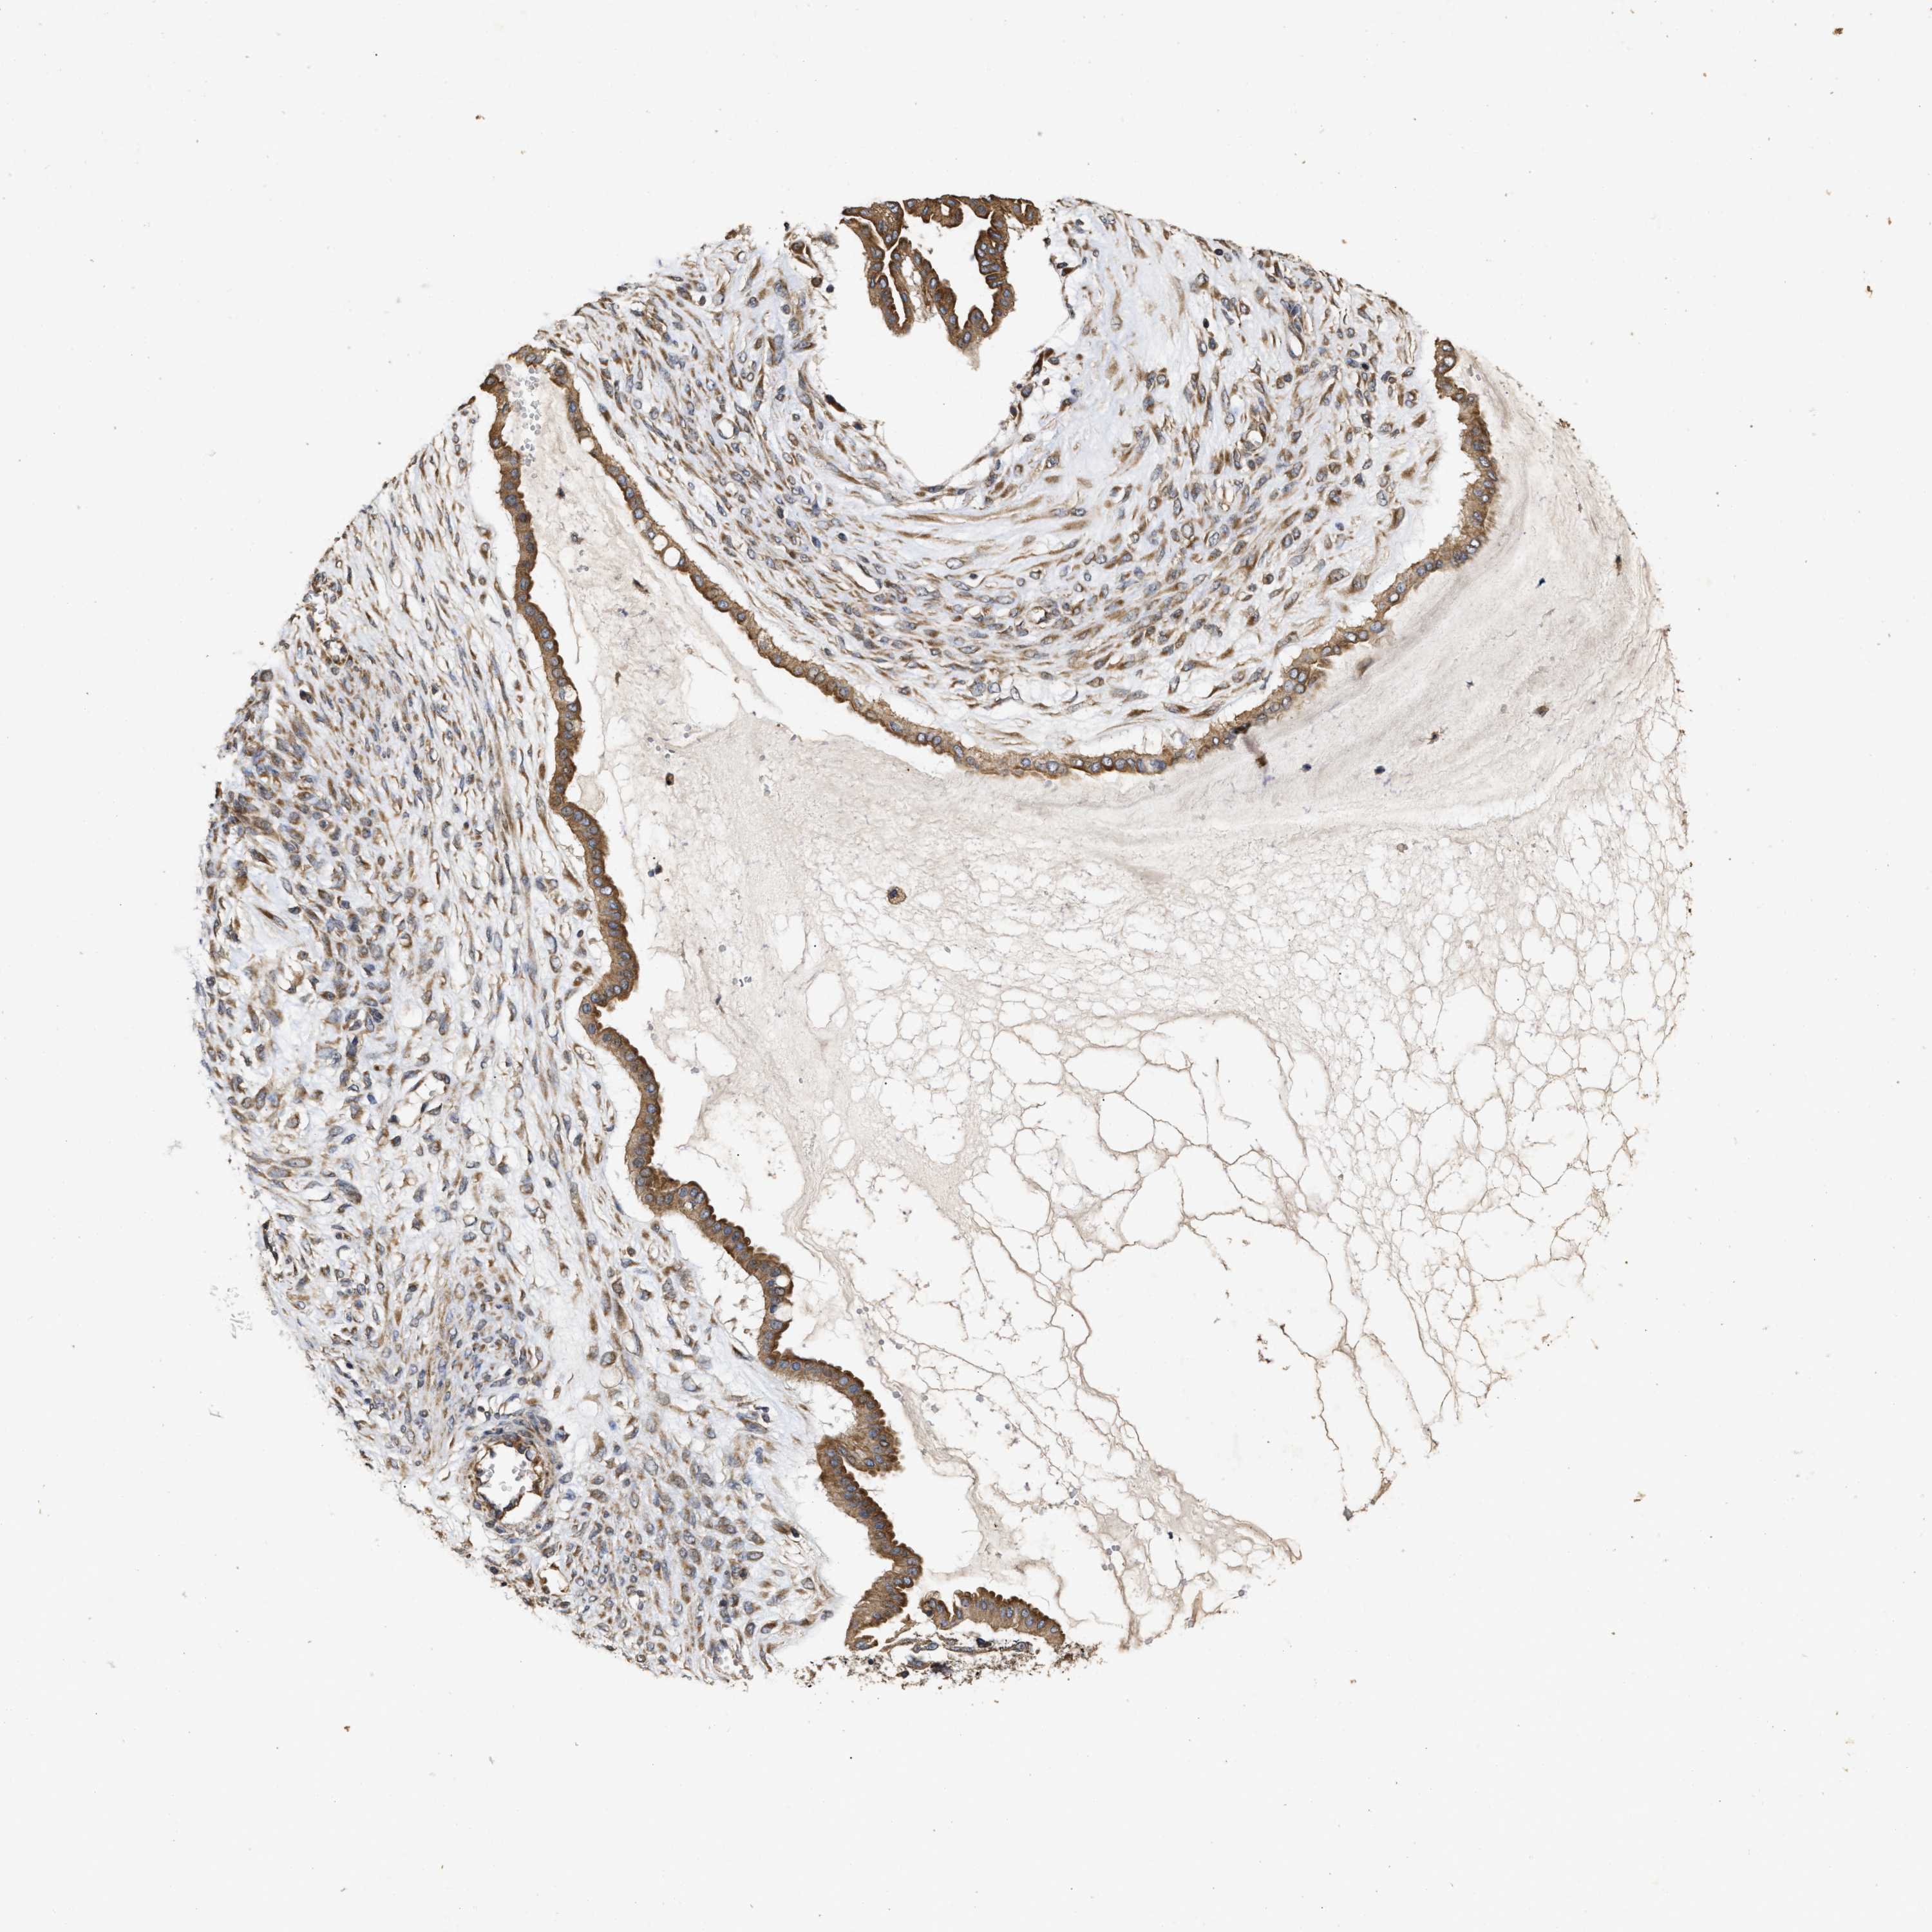

OVARIAN CANCER - Protein expressioni

A mouse-over function shows sample information and annotation data. Click on an image to view it in a full screen mode. Samples can be filtered based on level of antibody staining by selecting one or several of the following categories: high, medium, low and not detected. The assay and annotation is described here.

Note that samples used for immunohistochemistry by the Human Protein Atlas do not correspond to samples in the TCGA dataset.

Antibody stainingi

Antibody staining in the annotated cell types in the current human tissue is reported as not detected, low, medium, or high, based on conventional immunohistochemistry profiling in selected tissues. This score is based on the combination of the staining intensity and fraction of stained cells.

Each image is clickable and will lead to virtual microscopy that enables deeper exploration of all samples and also displays staining intensity scores, fraction scores and subcellular localization as well as patient and tissue information for each sample.

Antibody HPA018127

Antibody HPA027887

Antibody CAB012302

Staining

High

Medium

Low

Not detected

Intensity

Strong

Moderate

Weak

Negative

Quantity

>75%

75%-25%

<25%

None

Location

Nuclear

Cytoplasmic/membranous

Cytoplasmic/membranous,nuclear

Cystadenocarcinoma, serous, NOS

Carcinoma, endometroid

Cystadenocarcinoma, mucinous, NOS

Carcinoma, NOS